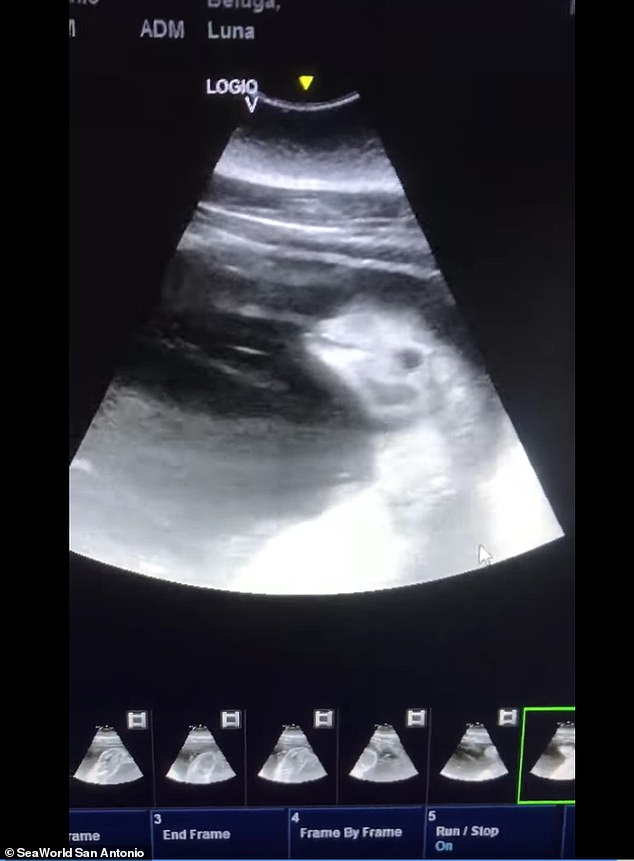

2021年01月16日一隻白鯨寶寶很快就要來到世界上啦~最近美國德州的聖安東尼奧海洋世界(SeaWorld San Antonio)發布喜訊,公園內有一隻叫Luna的白鯨媽媽,牠很快就要生產了。獸醫為Luna照了超音波,可以清晰看到小白鯨寶寶的可愛模樣。

▼Luna是於2000年在聖安東尼奧海洋世界出生的,這次懷孕牠將生下第4胎,前面的3次分娩都很順利,所以牠已經很有經驗了。Luna接受過專業的訓練,能在獸醫檢查時保持不動,所以才能拍到超音波。

▼從超音波可以看到,Luna肚子裡的白鯨寶寶已經發育得非常好,牠的輪廓很清晰,能看到眼睛和吻部,甚至像在微笑一樣,非常可愛: